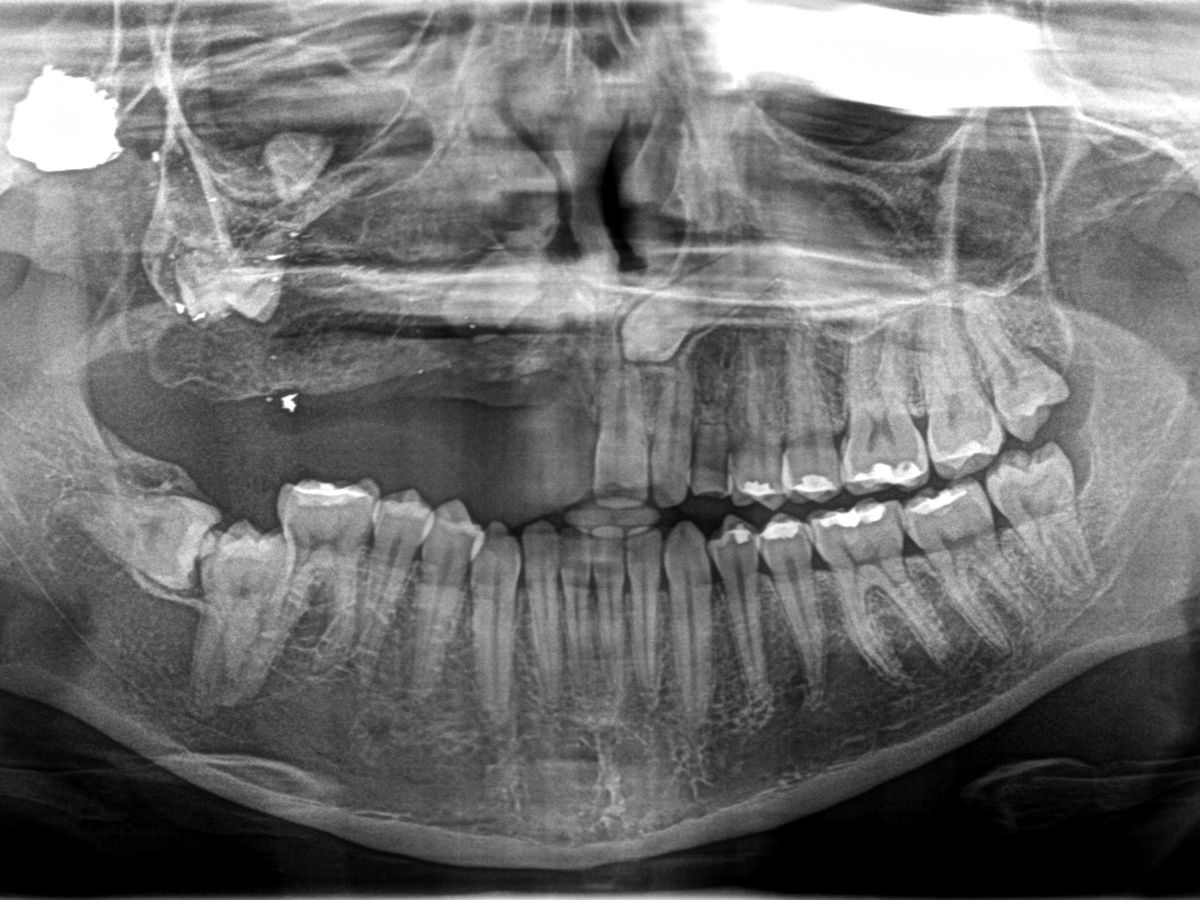

My name is Veronique Handal, and I am reaching out to share my story and seek your support. When I was just three years old, I experienced a life-altering event in Haiti: I was shot in the face. This tragic incident caused me to lose several teeth and left me with a bullet still lodged in my head. Over the years, I have lived with the physical and emotional challenges that come with these injuries.

This new plan still includes all the essential procedures I need—bone grafting, gum reconstruction, braces, and dental implants—but at a fraction of the original cost and in a different country. I am so relieved and excited to be one step closer to restoring my smile and moving forward with this life-changing treatment.